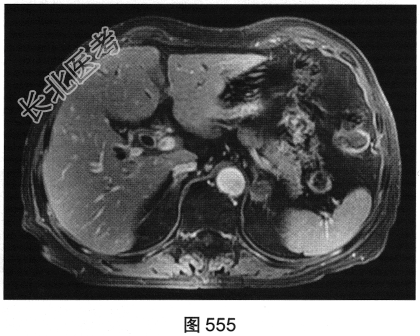

- 多项选择题3.[提示]MRI平扫+增强(图550~图555):T1WI正相位, 左侧肾上腺外侧肢可见类圆形T1WI稍高信号结节。T1WI反相位,结节信号明显减低。T2WI脂肪抑制, 结节呈均匀低信号。动态增强,动脉期结节轻度均匀强化, 静脉期结节呈相对低信号,延迟期结节呈相对低信号。可考虑的鉴别诊断为( )